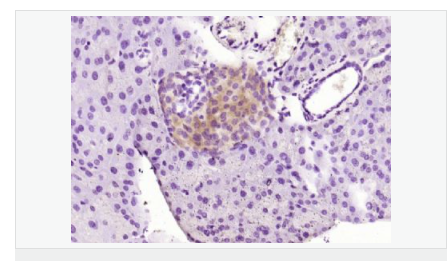

交叉反應:Mouse,Rat(predicted:Human,Dog,Pig,Horse,Rabbit,Sheep) 推薦應用:WB,IHC-P,IHC-F,IF,ELISA

產品應用WB=1:500-2000 ELISA=1:5000-10000 IHC-P=1:100-500 IHC-F=1:100-500 IF=1:100-500 (石蠟切片需做抗原修復)

免 疫 原KLH conjugated synthetic peptide derived from human SLC39A7:201-300/469

產品介紹Zinc is an essential cofactor for more than 50 classes of enzymes and is involved in protein, nucleic acid, carbohydrate, and lipid metabolism, plus the control of gene transcription, growth, development, and differentiation. Zinc cannot passively diffuse across cell membranes and requires specific transporters, such as SLC39A7, to enter the cytosol from both the extracellular environment and from intracellular storage compartments.

Tissue Specificity: